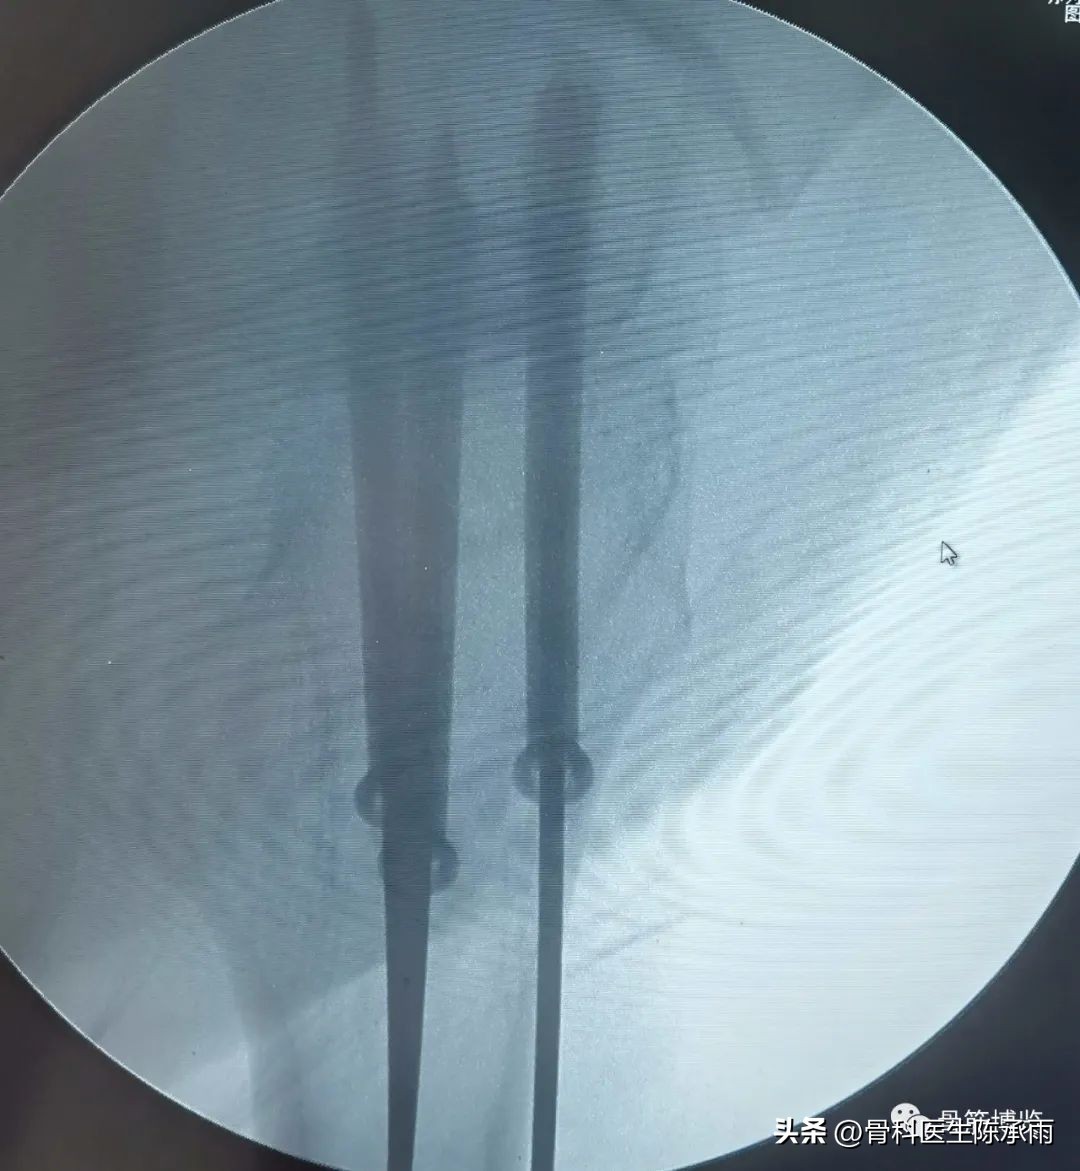

术前尝试闭合复位,效果满意,决定行经皮穿钉,但股骨颈角度不正常,颈部细小,很难容得下3枚直径7.3空心钉,最后1枚空心钉部分切出股骨颈上缘。